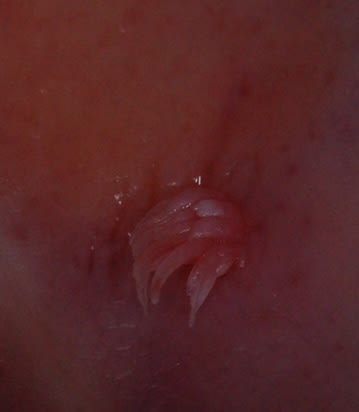

Après avoir vu quelques uns poster des énigmes, voici des photos du palais d’un patient.

De quoi s’agit il ?

C est un papillome verruqueux.

VPH (Virus Papillome Humain)